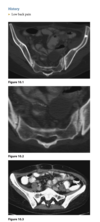

A sagittal fast spin-echo, T2-weighted fat-suppressed

MR image through the lateral joint compartment

(Fig. 2.14.3) shows high-signal-intensity areas in the

subchondral regions of the midportion of the lateral femoral condyle and the posterolateral tibial plateau,

the so-called “kissing contusions”

Bone

impaction from transient subluxation results in

the characteristic osseous contusions involving the posterolateral tibial plateau and midportion of the

lateral femoral condyle (i.e., “kissing contusions”).